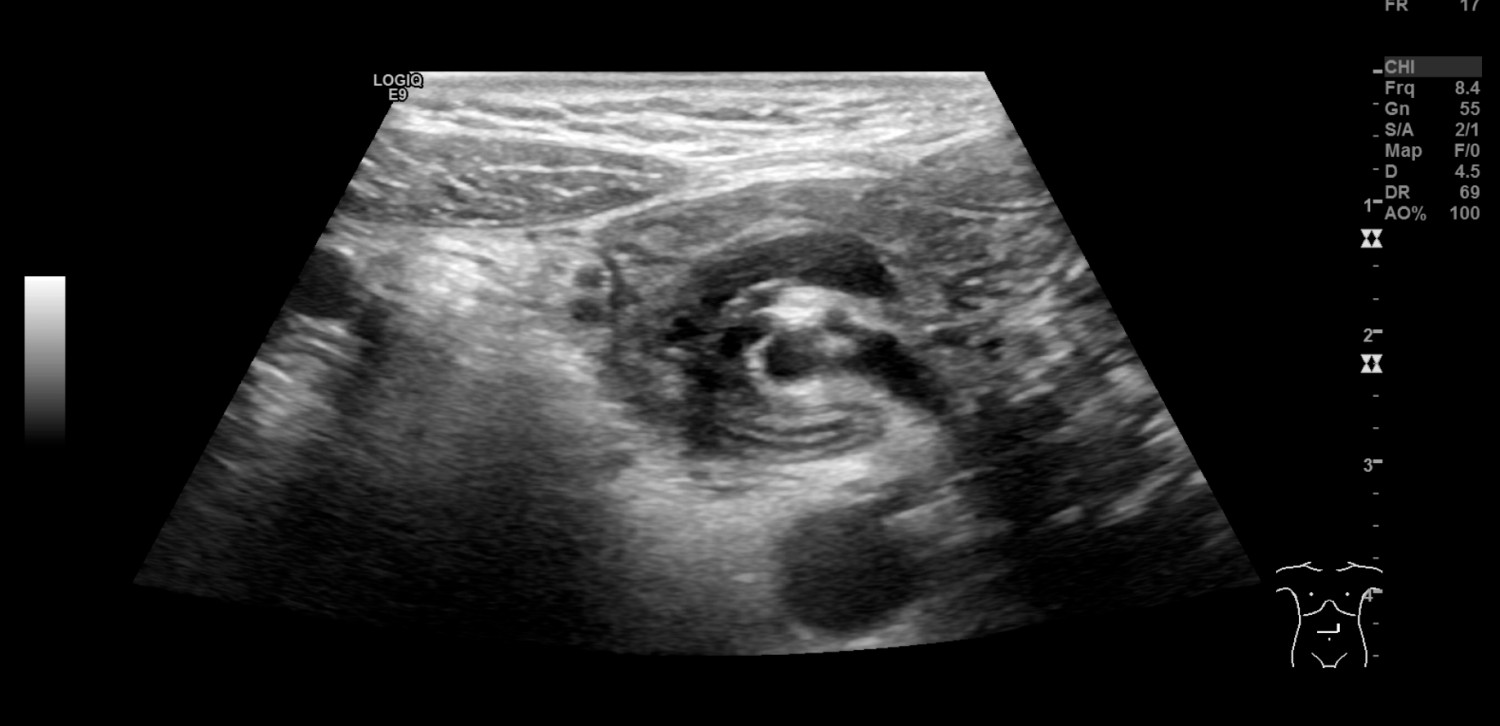

En såpass uttalt og akutt forverring passet ikke med tidligere vurderte diagnoser som abdominal migrene, gastroøsofageal refluks eller obstipasjon, og differensialdiagnostisk ble ventrikkelretensjon eller arteria mesenterica superior-syndrom vurdert. Ved innkomst startet man behandling med erytromycin (Ery-Max) mikstur 3 mg/kg for å stimulere til ventrikkeltømming, intravenøs NaCl og glukoseløsning tilsatt natrium og kalium, samt kaliummikstur 10 ml x 3 peroralt. Ultralyd abdomen ble utført av radiologisk lege i spesialisering fredag kveld, og det ble beskrevet virvellignende rotasjon (whirl sign) i epigastriet som involverte vena og arteria mesenterica superior (figur 1). Legen mistenkte intestinal malrotasjon og anbefalte i første omgang kontrollultralyd av erfaren barneradiolog på dagtid. Det ble også bemerket spiss vinkel mellom aorta og proksimale del av a. mesenterica superior, som ved mulig arteria mesenterica superior-syndrom. Det var normale funn ved røntgen oversikt abdomen.

Gjennom helgen ble jenta observert. Hun hadde bedre allmenntilstand, lite magesmerter og ingen episoder med oppkast. Elektrolyttnivået ble raskt normalisert etter påbegynt væskebehandling. Mandag formiddag ble det gjort ultralydkontroll av en erfaren barneradiolog som bekreftet funn av virvellignende rotasjon (figur 1 og 2) og som mistenkte ledsagende volvulus (tarmslyng som følge av at et tarmsegment vris rundt sin egen akse). Diagnosen ble bekreftet med røntgen øsofagus, ventrikkel og duodenum som viste kontrastpassasje til proksimale tynntarm, men ikke videre (figur 3). Overgangen mellom duodenum og tynntarm lå like til venstre for midtlinjen, kaudalt for nivå med bulbus duodeni, noe som indikerte malrotasjon med volvulus. Man hadde omsider funnet forklaringen på pasientens langvarige plager (figur 4).

Ved ultralydundersøkelse ligger normalt v. mesenterica superior til høyre for a. mesenterica superior. Hvis venen ligger til venstre eller foran arterien, gir det sterk mistanke om malrotasjon. Sensitivitet er angitt til 67–100 % og spesifisitet til 83–92 % (7). Ved unormalt leie påvist på ultralyd bør man gå videre med røntgen av øsofagus, ventrikkel og duodenum. Hos vår pasient så man på ultralyd det såkalte «whirl sign», som er regnet som 100 % spesifikt for midttarmsvolvulus (7): Duodenum, proksimale del av tynntarm og v. mesenterica superior snurrer rundt a. mesenterica superior. Bakenforliggende årsak er malrotasjon og et kort mesenterium. Midttarmsvolvulus gir en duodenal, altså en helt proksimal obstruksjon, og røntgen oversikt abdomen kan således vise helt normale funn, mens barnet likevel har en akutt, operasjonstrengende tilstand.

Ultralyd med doppler, der man kan påvise den virvellignende rotasjonen, er i trenede hender svært nyttig i diagnostikken (3) og er ofte den første bildeundersøkelsen barnet får gjort. Røntgen av øsofagus, ventrikkel og duodenum er gullstandard for diagnostikk av malrotasjon og bør alltid utføres som øyeblikkelig hjelp ved mistanke om malrotasjon – selv ved negativ ultralyd (6, 7). Til tross for at man i løpet av radiologispesialiseringen skal ha opplæring i ultralydundersøkelser på barn, kan man ikke forvente at alle kjenner til ultralydfunn ved uventet volvulus. De færreste som ikke jobber med barn, vil noen gang se det. Man bør imidlertid, både som kliniker og radiolog, være spesielt oppmerksom på babyer/barn med gallefarget oppkast. Da må malrotasjon og volvulus alltid mistenkes. Det kan være subtile abdominale symptomer initialt, og det er som regel først sent i forløpet at barnet utvikler blodig avføring og peritonitt (6). Det kan da allerede foreligge irreversibel iskemisk skade av midttarmen. Ved rask, presis diagnostikk og påfølgende kirurgi ved påvist malrotasjon kan en potensielt livstruende tilstand få et vellykket utfall.